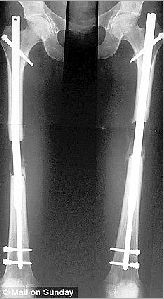

手术图片 托马斯的照片

实施手术所需要的不仅是金钱,还有毅力。“拉骨增高”手术首先要在托马斯的大腿骨上钻个洞,以便插入28厘米长的可伸缩不锈钢杆,钢杆两端通过螺钉和腿骨紧紧固定,然后生将他的腿骨从大腿中间锯成两截。据悉,托马斯断裂腿骨间的空隙,会在术后8个月被长出的新骨逐渐填满,腿骨上的螺钉会在18个月后通过第二次手术移除掉。除了手术后的疼痛,患者还须面临由于肌肉和肌腱位置改变,所带来的其他不适。专家指出,腿骨被拉长的“极限长度”,是由患者的身体可接受程度而决定。